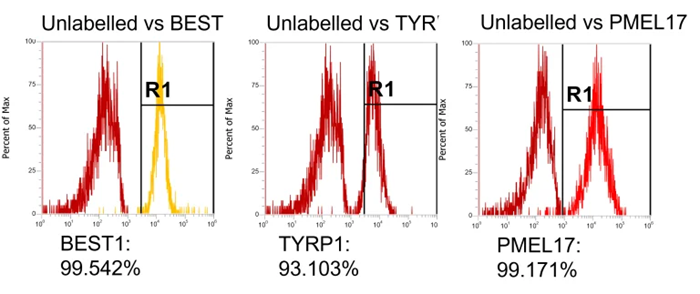

High expression of the RPE markers BEST1, TYRP1, and PMEL17 in flow cytometry data indicates a highly pure, differentiated population.

Expression of RPE markers, TYRP1, PMEL17 and BEST1. Image Credit: Newcells Biotech

Protein expression of RPE cells using flow cytometry after TEER plateaued. PMEL17 – a protein which is expressed in melanosome precursors (>95% expression). TYRP1 – is expressed in mature RPE and is located in melanosomes (>85% expression). BEST1 – is a Ca2+-regulated chloride channel and is a critical for normal phagocytotic function (>98% expression). Image Credit: Newcells Biotech